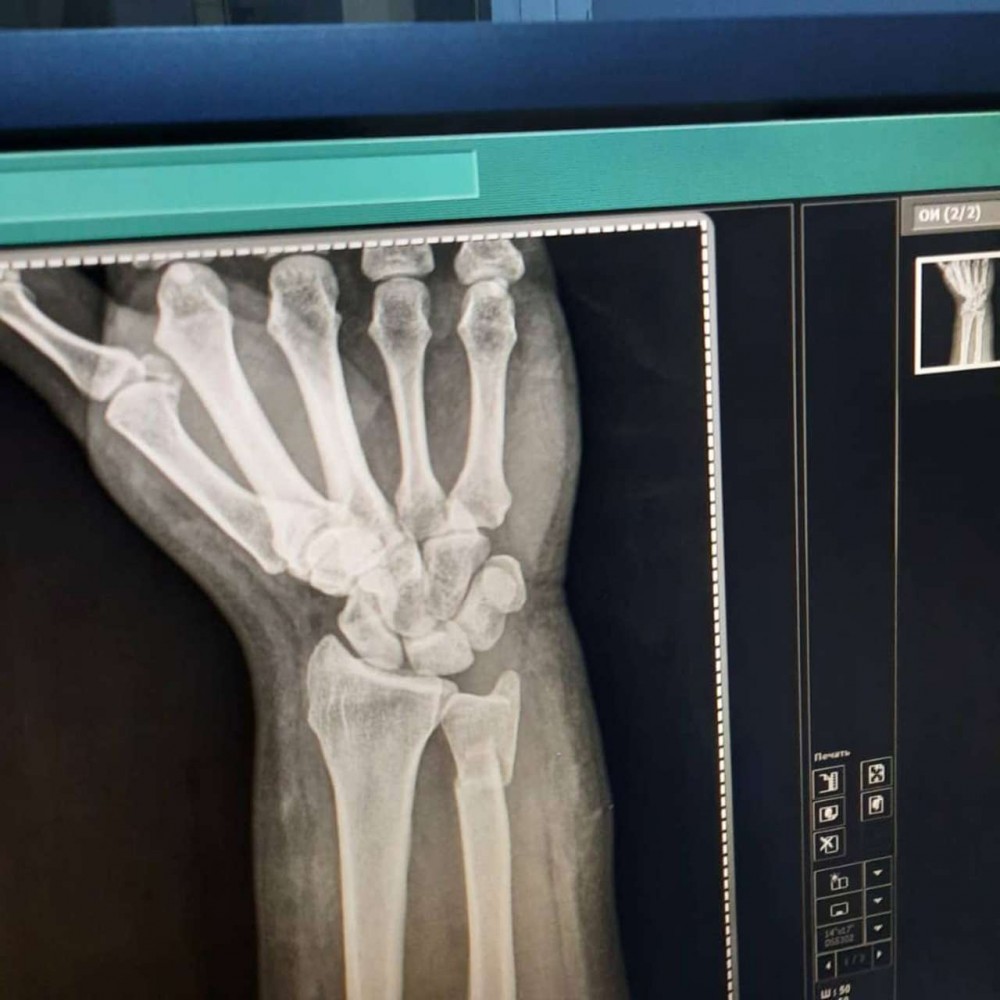

Azərbaycanlı aparıcının biləyi qırıldı - FOTOLAR

Tanınmış aparıcı Aytən Səfərovanın başına iş gəlib.

32gun.az xəbər verir ki, aparıcının bilək sümüyü sınıb. Bu barədə Səfərova instaqramda məlumat yayıb. O bildirib ki, bu günlərdə anası ağır əməliyyata hazırlaşır:

“Çox çalışdım ki, könlümü fərəh tutum, fikirləşdiyimi büruzə verməyim, özümü “sındırmayım”, lakin sümüyümü sındırdım. Həkimlər vaxtında müdaxilə etdilər. Hələ ki, ağrıkəsicisiz mümkün deyil, amma biz güclü qadınıq. İnşallah bu da keçər. Özünüzü qoruyun”.